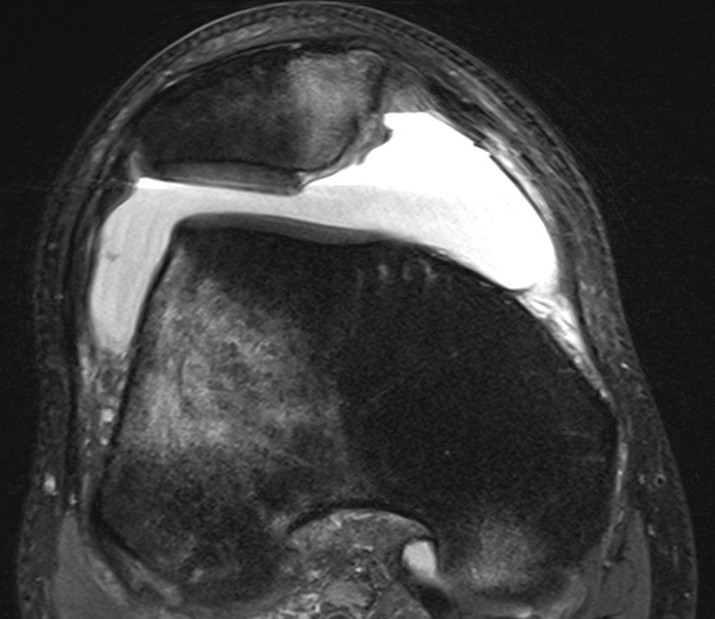

Small chondral fracture in notch from medial facet patella, and avulsion of MPFL from patella

Large chondral fracture from medial facet of patella